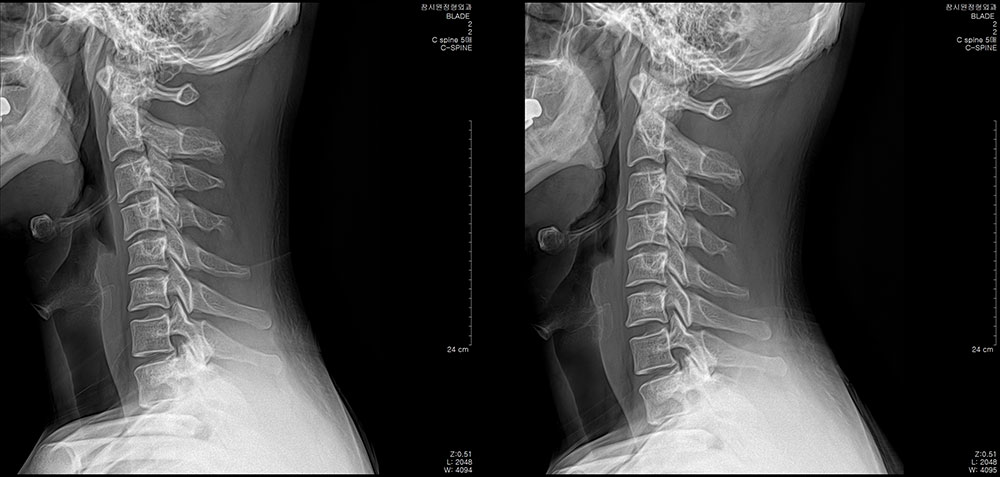

ÃÊÀ½ÆÄÁø´Ü ÇÁ·Ñ·ÎÄ¡·á ü¿ÜÃæ°ÝÆÄ µµ¼öÄ¡·á ¿ÀÇǽºÁúȯ °üÀý¿°Ä¡·á Ä¡·á Àü/ÈÄ »çÁø Ä¡·á Àü/ÈÄ »çÁø °ÅºÏ¸ñ µµ¼öÄ¡·á 10ȸ ÈÄ °ÅºÏ¸ñ µµ¼öÄ¡·á 8ȸ ÈÄ Ç㸮ÅëÁõ¡¤´Ù¸®Àú¸² µµ¼öÄ¡·á 10ȸ ÈÄ °ñ¹Ý Ʋ¾îÁü µµ¼öÄ¡·á 12ȸ ÈÄ Ã´Ãß Ãø¸¸Áõ ¹× Ç㸮ÅëÁõ µµ¼öÄ¡·á 15ȸ ÈÄ